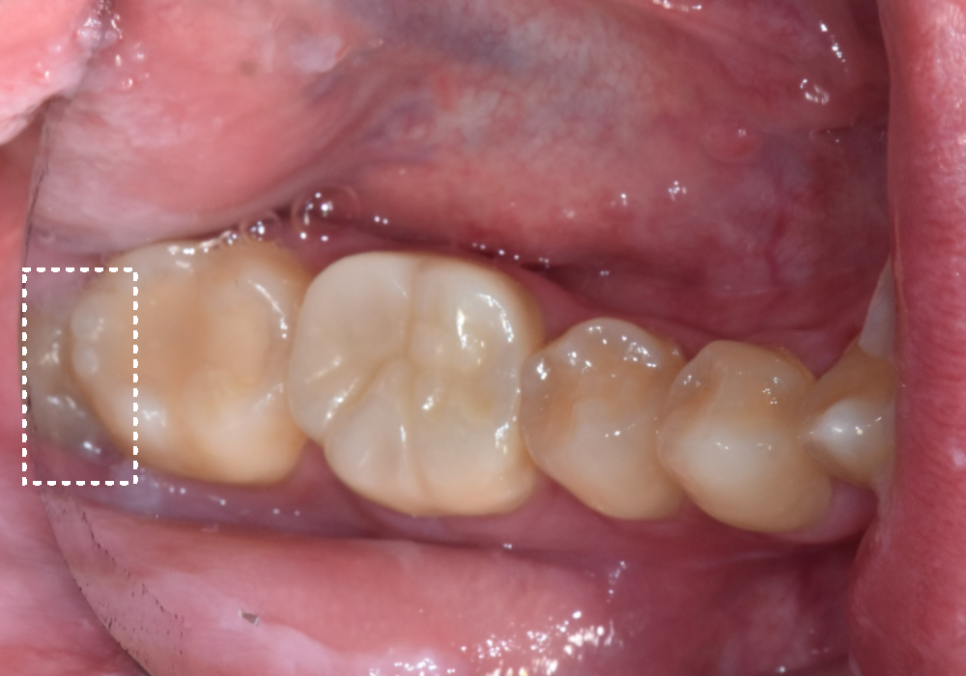

얼마 전 한 환자분께서

오른쪽 아래 어금니 쪽에

음식물이 자꾸 끼고

욱신거린다는 증상으로 오셨습니다.

입안을 겉에서만 보았을 때는

사랑니(#48)가 머리만 살짝 보이고 있어서

큰 문제가 없어 보였죠.